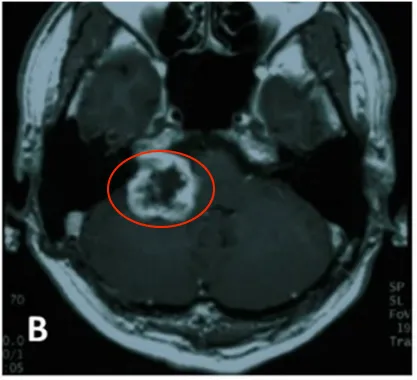

B.2005年8月,第一次手术后、伽玛刀治疗前的MR图像。